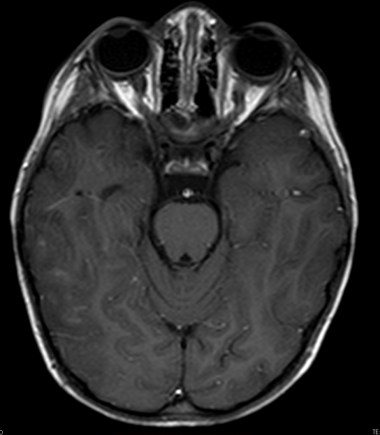

- Secuencias potenciadas en T2 y FLAIR muestran lesiones hiperintensas, de afectación bilateral, irregular, mal definidas, de tamaño variable y asimétricas que son la expresión de áreas de inflamación y desmielinización de la sustancia blanca. Las lesiones afectan sobre todo a la sustancia blanca cerebral, pero también a la sustancia gris y núcleos de la base y a médula espinal.

Las localizaciones cerebrales más frecuentemente afectadas son la sustancia blanca profunda (frontal y parietal sobre todo), sustancia blanca yuxtacortical, sustancia blanca periventricular, cuerpo calloso, sustancia gris cortical, tronco del encéfalo y cerebelo.